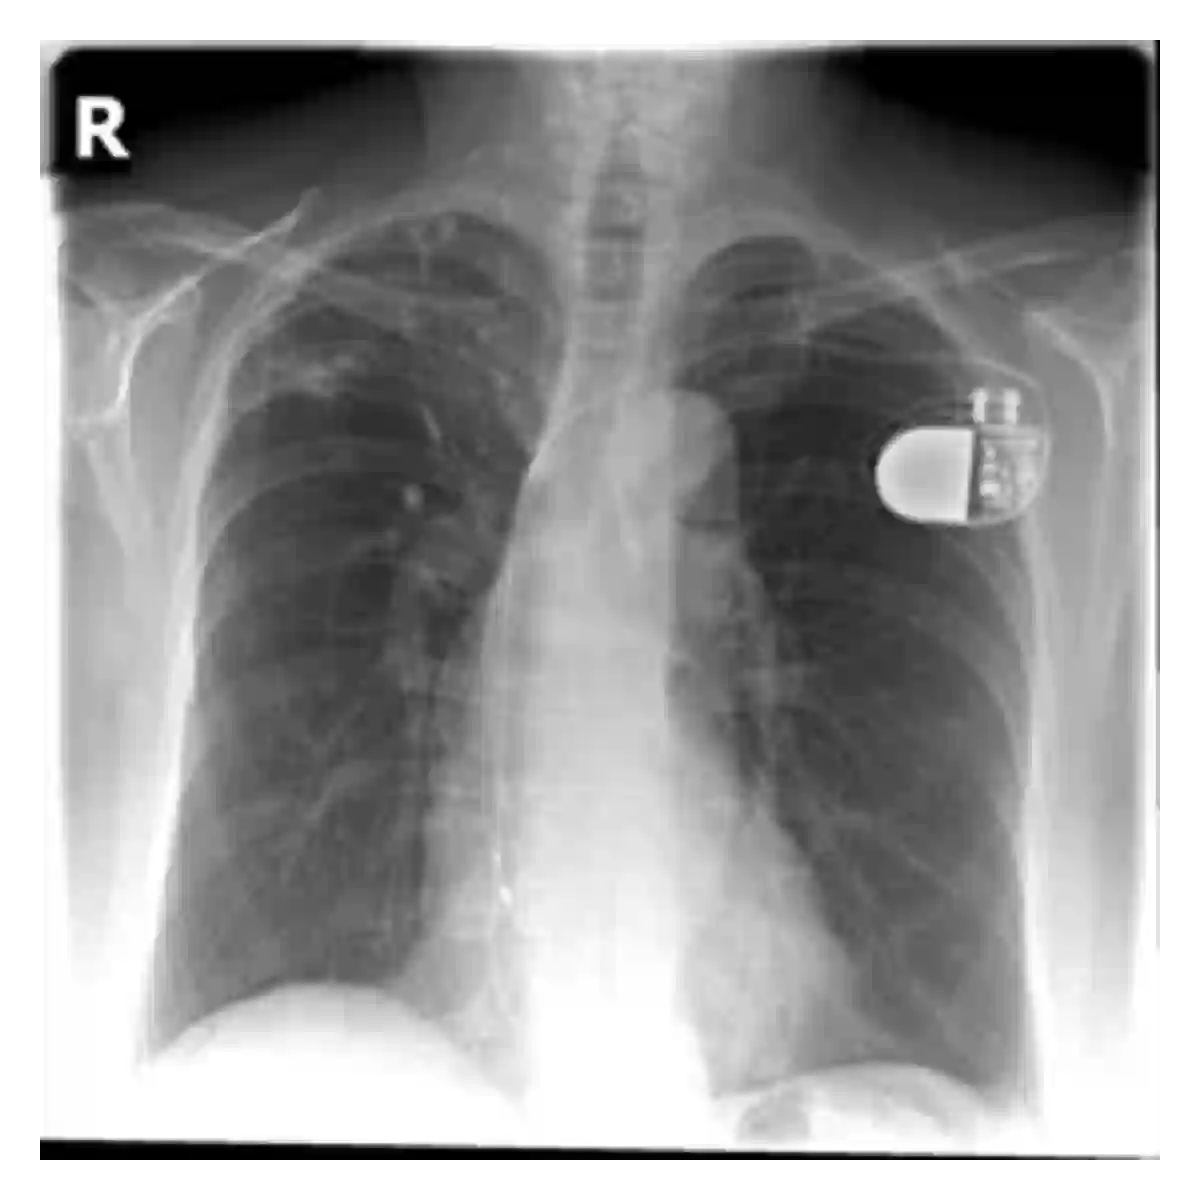

The evaluation of infectious disease processes on radiologic images is an important and challenging task in medical image analysis. Pulmonary infections can often be best imaged and evaluated through computed tomography (CT) scans, which are often not available in low-resource environments and difficult to obtain for critically ill patients. On the other hand, X-ray, a different type of imaging procedure, is inexpensive, often available at the bedside and more widely available, but offers a simpler, two dimensional image. We show that by relying on a model that learns to generate CT images from X-rays synthetically, we can improve the automatic disease classification accuracy and provide clinicians with a different look at the pulmonary disease process. Specifically, we investigate Tuberculosis (TB), a deadly bacterial infectious disease that predominantly affects the lungs, but also other organ systems. We show that relying on synthetically generated CT improves TB identification by 7.50% and distinguishes TB properties up to 12.16% better than the X-ray baseline.